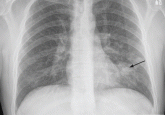

ArticleA 37-year-old man with a chronic coughAuthor:Sandeep M. Patel, MDPublish date: February 1, 2012When asked, he revealed that he had been diagnosed with human immunodeficiency virus infection but had not been taking his medication.Read More